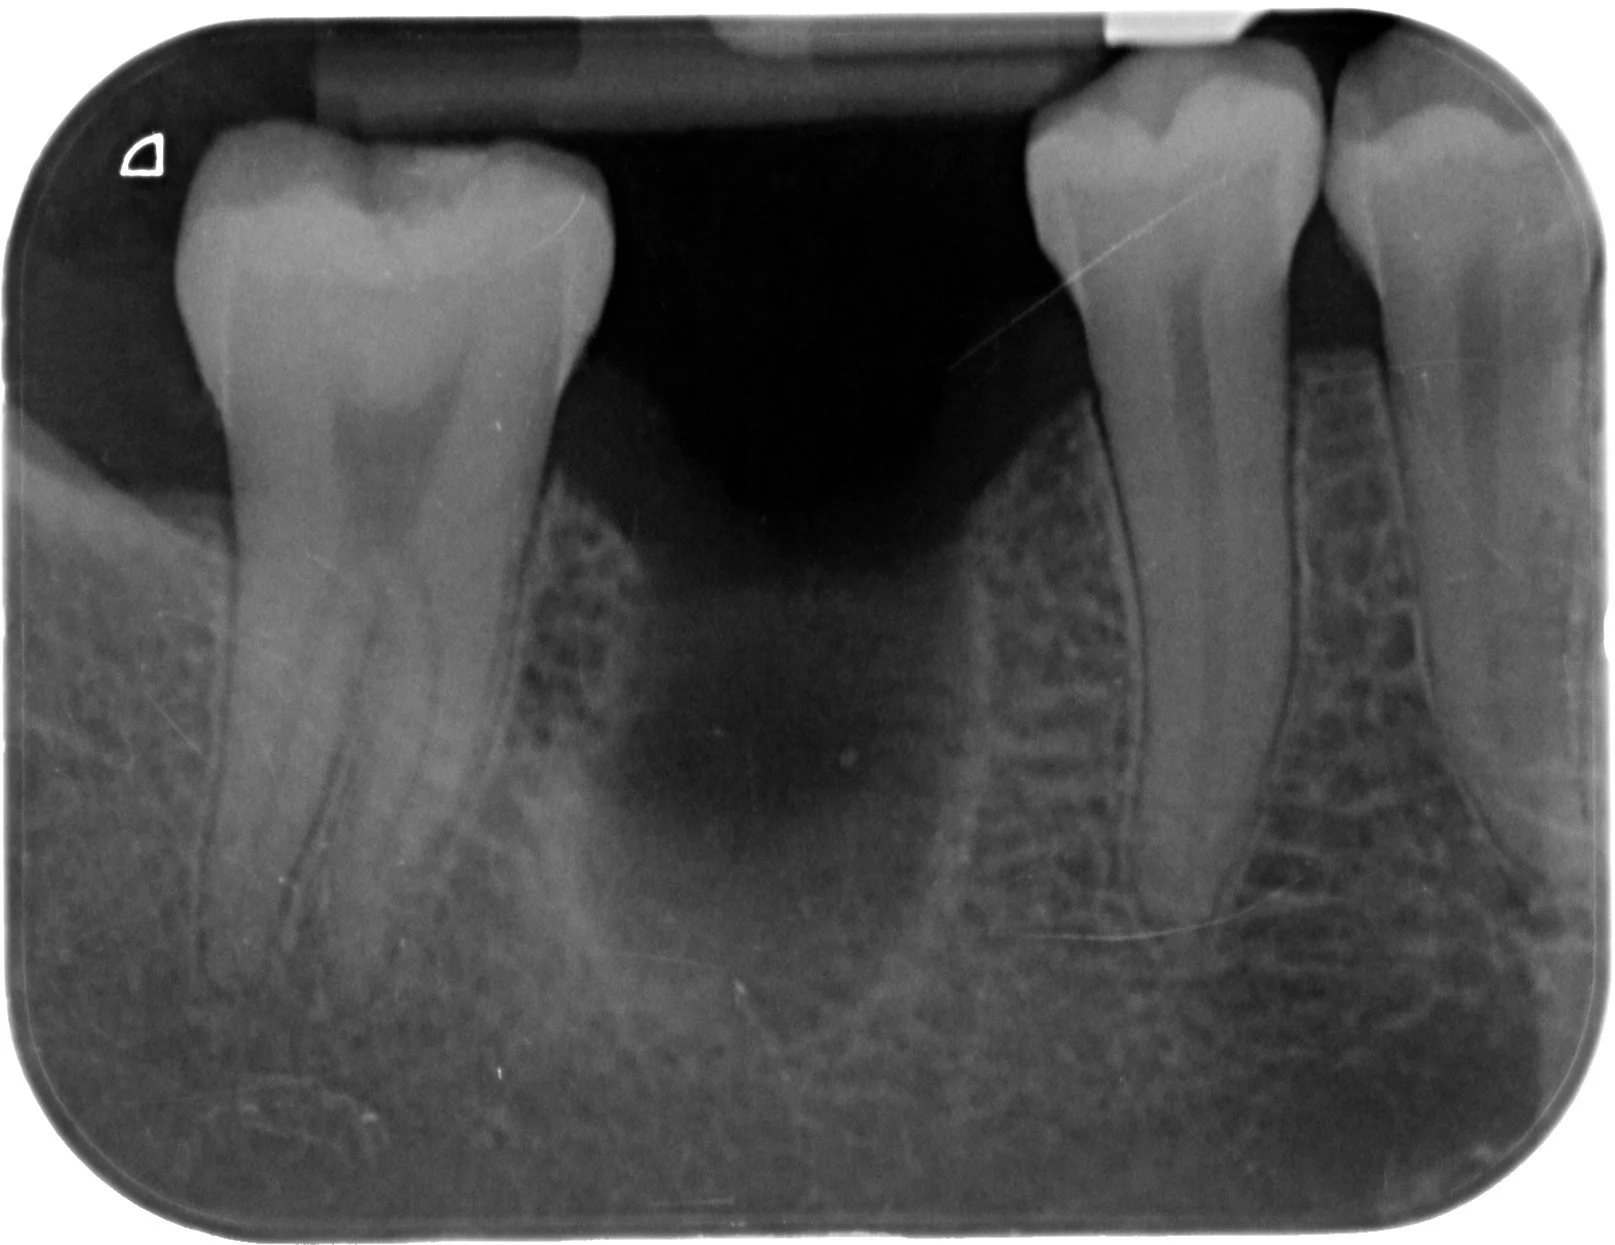

Relativement récents, les bridges collés cantilever postérieurs constituent une alternative fixe, fiable et véritablement minimalement invasive aux implants dans les secteurs postérieurs. Cette thérapeutique qui repose sur des indications bien précises est parfois débattue avec passion sur les réseaux sociaux ou dans les congrès scientifiques. Cependant des études cliniques existent, tout comme des recommandations validées dans des journaux internationaux. Leur succès repose sur des préparations et des principes biomécaniques rigoureux, pourtant simples à intégrer au quotidien. Cette intervention propose un guide clair et opérationnel incluant indications, étapes clés, protocoles d’adhésion et réglages occlusaux pour les mettre en œuvre avec confiance et reproductibilité.